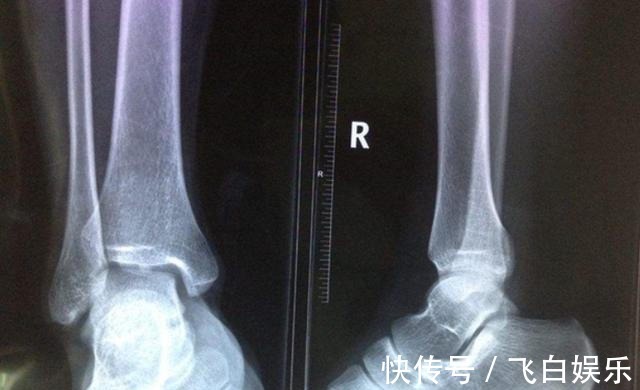

吴女士很不理解,明明女儿吃饭是很正常的,补钙也补了,为什么就是长不高呢?后来去医院做了一个检查之后才发现这竟然是骨骼疑似闭合,这真是给了吴女士一个晴天霹雳。不过好在孩子的骨骼还没有完全闭合,如果抓住机会的话还能够长一长个子。吴女士倒吸了一口凉气,看来想要给孩子长个儿得抓紧了。虽然说骨线闭合是一个比较严重的问题,但是孩子一旦出现这种情况的话,在这之前肯定是有一些信号的。当孩子身上有这3个信号的时候一定不要放弃,把握机会的话个子还是有可能窜一窜。